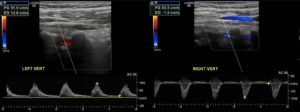

The worst outcome of subclavian artery stenosis is subclavian steal syndrome. In this condition, neurological symptoms occur because of the subclavian artery stenosis. Simply, when the arm needs more blood it “steals” it from the brain. The steal happens through the vertebral arteries. Blood will in these arteries will flow in the opposite direction. Instead of going to the brain, it will flow to the arm.

The next step is to use imaging. Imaging will make the diagnosis of the narrowing in the subclavian artery. Obviously, CT and MR are the best types of imaging for this. Then, imaging should identify the reverse flow in the vertebral artery. Duplex ultrasonography is the best type of imaging for identifying flow direction. Here is an example: